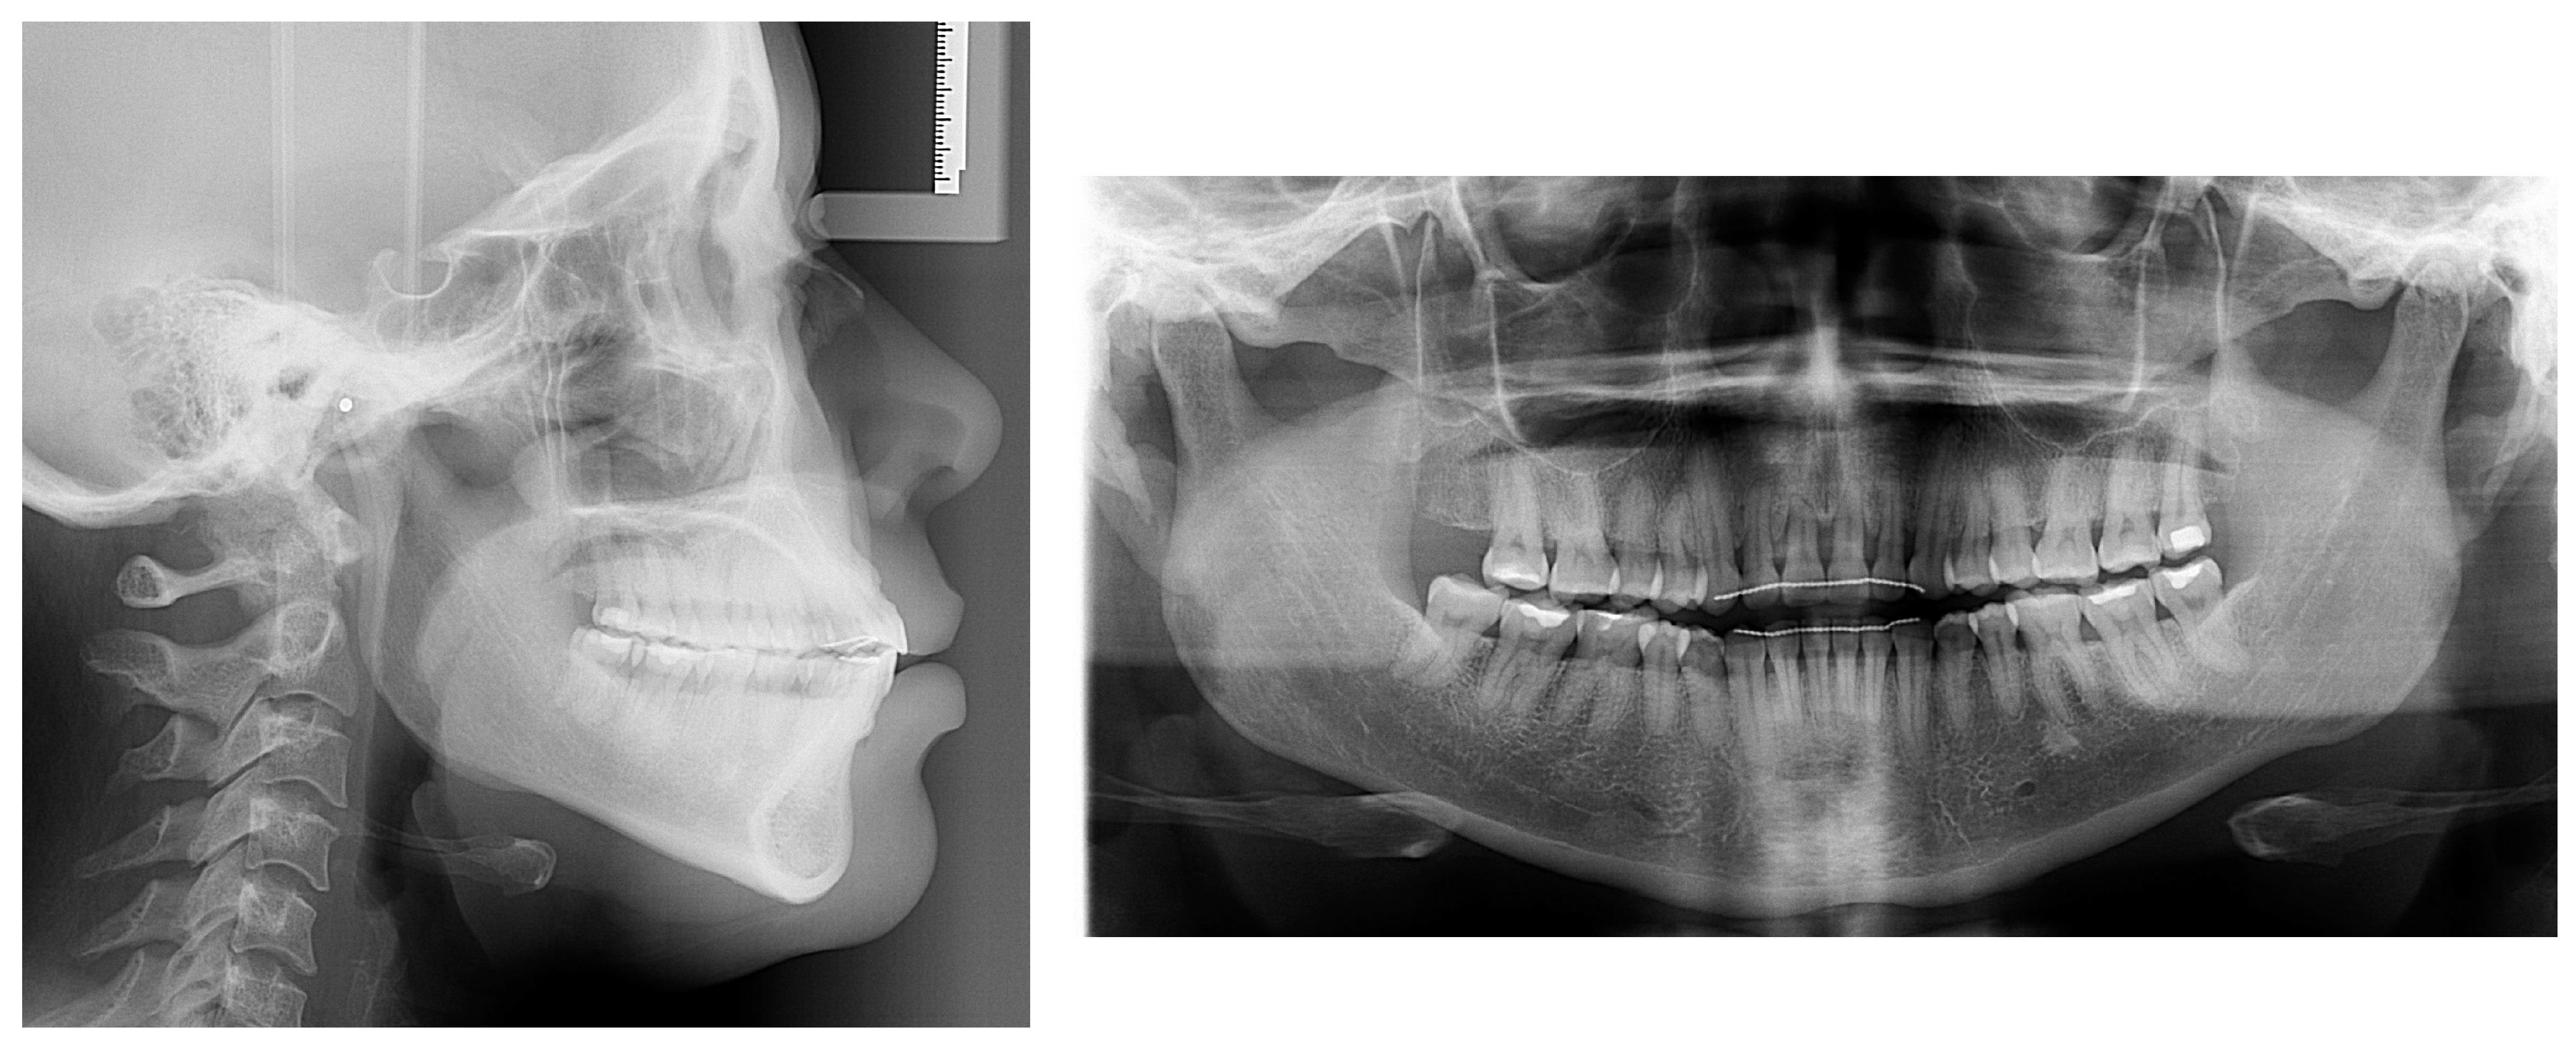

2. Case Presentation

2.1. Diagnosis and Etiology